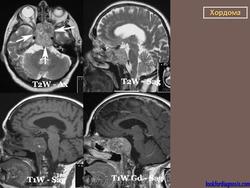

Хотя хордома может возникнуть в любом отделе позвоночного столба, наиболее излюбленными местами локализации этой опухоли являются 1-й шейный позвонок и пояснично-крестцовый отдел позвоночника. Это достаточно редкое заболевание. Чаще всего хордома возникает у мужчин среднего возраста. По данным рентгенографии, компьютерной томографии, магнитно-резонансной томографии можно поставить только предварительный диагноз. Для подтверждения диагноза необходимо проведение биопсии (забор кусочка опухолевой ткани с проведением микроскопического исследования). Лечение хирургическое. Прогноз зависит от размеров опухоли, наличия осложнений и общего состояния пациента.

Хордома развивается из персистирующих остатков хорды. Преимущественная локализация хордомы - это область сфеноокципитального сочленения и крестцово-копчиковый отдел позвоночника. Сведения о частоте отдельных форм хордомы весьма разноречивы.

Рентгенологическая картина хордом характеризуется наличием очага деструкции, захватывающего ряд позвонков. Костный дефект представляется однородным, либо крупнокамерным за счет тонких костных полосок. Показаны боковые рентгенограммы крестца, на которых при хордоме определяется увеличение передне-заднего размера крестца за счет экспансивного роста опухоли. В отдельных случаях в опухоли прослеживаются небольшие костные включения, которые могут служить поводом для ошибочной диагностики тератом, особенно в детском возрасте. (В детском возрасте тератомы встречаются часто, их соотношение с хордомами, по данным М. В. Волкова, 60:2).

Для хордом различных локализаций, выявлены наиболее характерные симптомы. Так, селлярные хордомы чаще проявляются глазодвигательными нарушениями (III нерв - 43%, VI нерв - 59%), и у трети больных эндокринными нарушениями (чаще гипотиреоз, гипокортицизм, гипогонадизм). У больных с хордомами ската типичными симптомами были поражение отводящего (79%), тройничного нерва (65%) и туловищная атаксия (55%). Симптомы поражения VII, VIII, IX или X черепных нервов были у трети больных с этой локализацией опухоли. Клиника при локализации хордом в краниовертебральной области представлена, как правило, характерным симптомокомплексом. Поражаются черепные нервы с VI по XII (VI -53%, VII - 33%, VIII - 27%, IX и X - 77%, XI - 48%, XII - 62%), у части больных имеют место тетрапарез или гемипарез. Нередко обращает на себя внимание вынужденное положение головы или ограничение объёма движений (поворотов и наклонов головы), боль и "хруст" в шее.